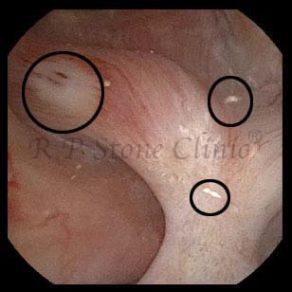

These images are taken as snap shots from the video recording of RIRS Surgery done at our hospital. These are Randall’s Plaques seen with Digital FLEX XC & Digital FLEX XC S. The cream or whitish patches are seen on the tips of RENAL PAPILLAE as seen in images below.

The Below Images Show Small Stones attached to the Renal Papillae.